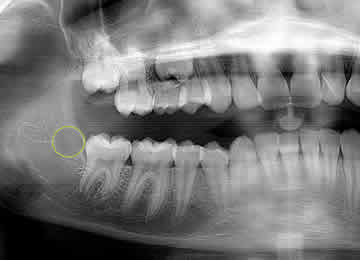

Zero3® technology has built-in controls to ensure the ablation procedure results in warming of targeted tooth buds (circled) from the center outwards. This patented feature is designed to dramatically reduce the risk of adversely effecting adjacent tissue while clinically inducing 3rd molar agenesis.

Zero3® TBA technology controls the one-minute ablation process by warming targeted tooth bud tissue (circled) from the center outward. This clinically induces complete molar agenesis with minimal risk of adversely affecting adjacent tissues.